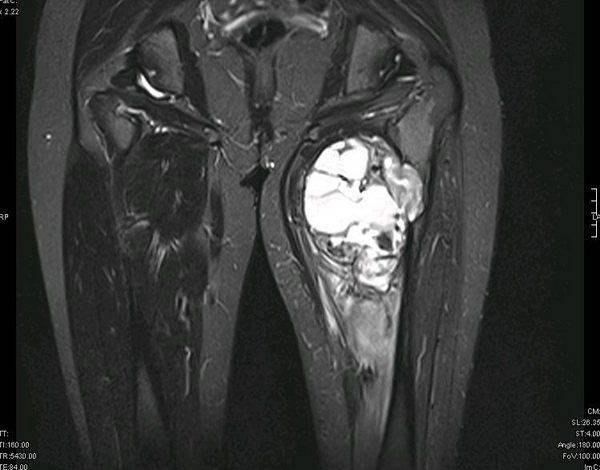

Чаще всего саркома мягких тканей поражает конечности, а именно, область бедер.

К признакам заболевания можно отнести появление уплотнений в конечностях, которое сопровождается онемением и покалыванием. Сначала новообразование безболезненное, но позже может появиться болевой синдром. Пациент чувствует общее недомогание, тошноту, а также давление опухоли на соседние ткани и нервные окончания.

- Магнитно-резонансная томография – дает возможность отслеживать метастазы раковых образований, и исследовать содержимое опухоли.

Диагностика саркомы предполагает комплексное обследование, которое направлено на обнаружение опухоли, верификацию диагноза и определение стадии заболевания. Первый этап – это обнаружение опухоли. Для этого проводится внешний осмотр и используются методы медицинской визуализации — УЗИ, КТ, МРТ. Эти методы не только позволяют обнаружить опухоль как таковую, но и определить ее взаимоотношение с окружающими тканями, например, есть ли распространение на соседние органы, вовлечены ли в процесс кровеносные сосуды и т. д.